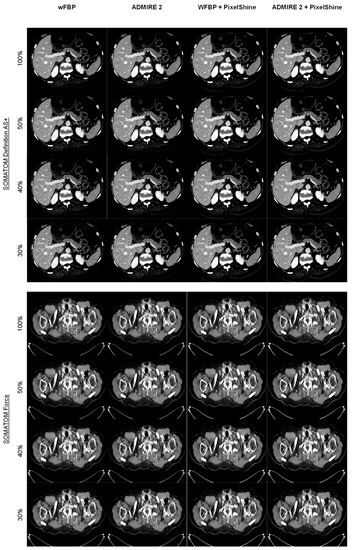

3.2.1. Subjective Image Quality

3.2.2. Objective Image Quality